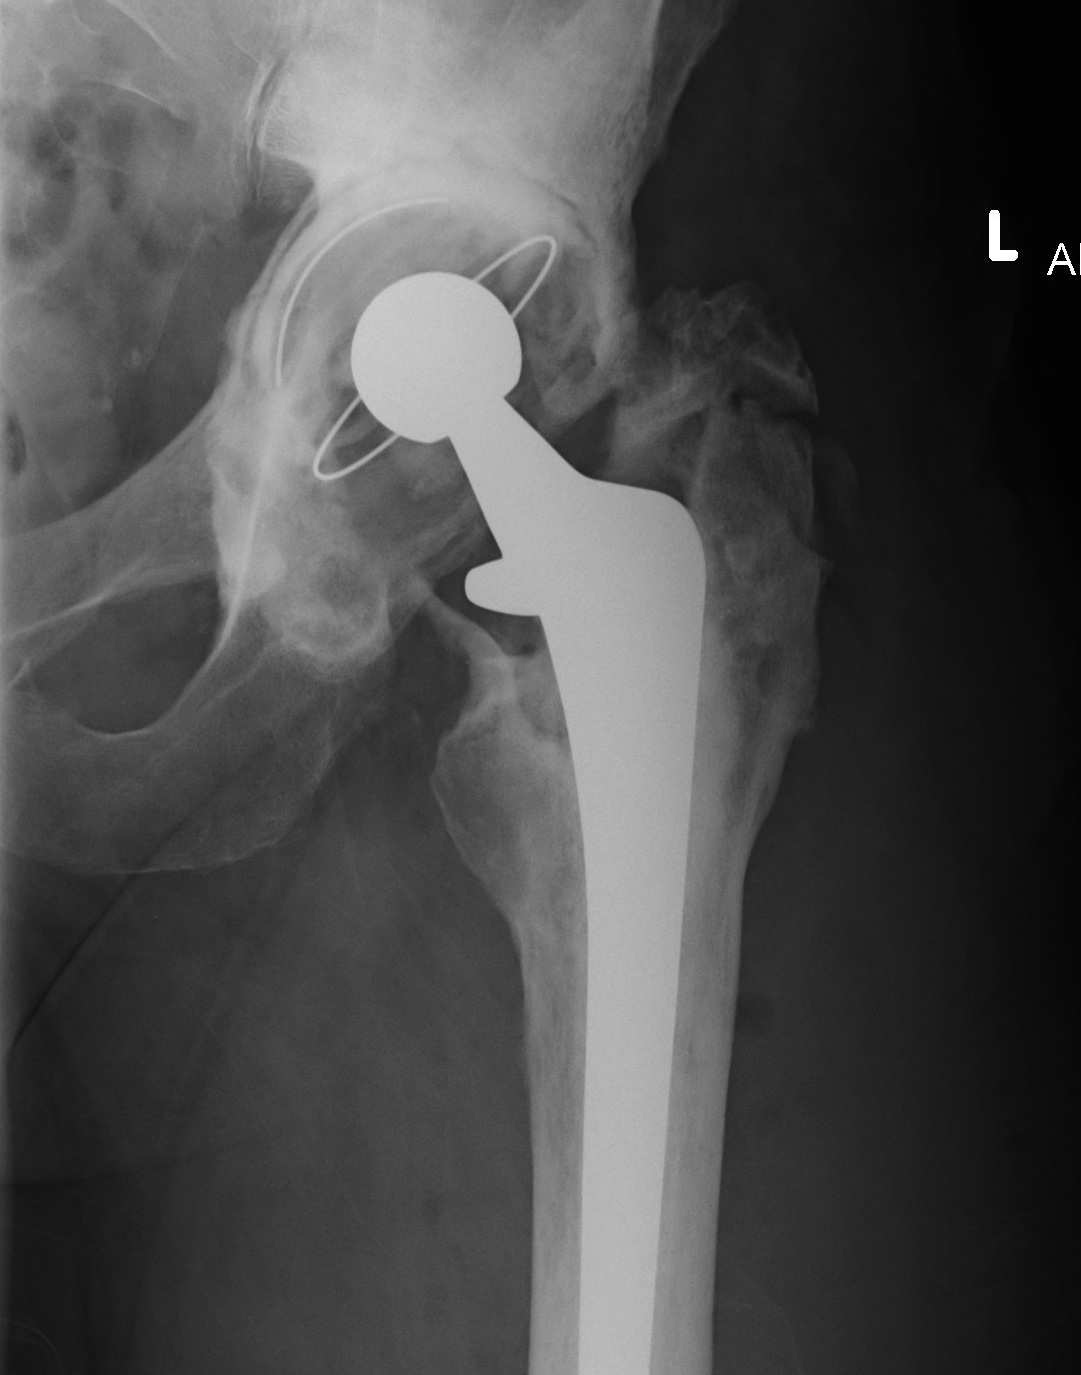

1. Infection

Peters et al J Arthroplasty 2009

Management

Incidence

Knee > Hip